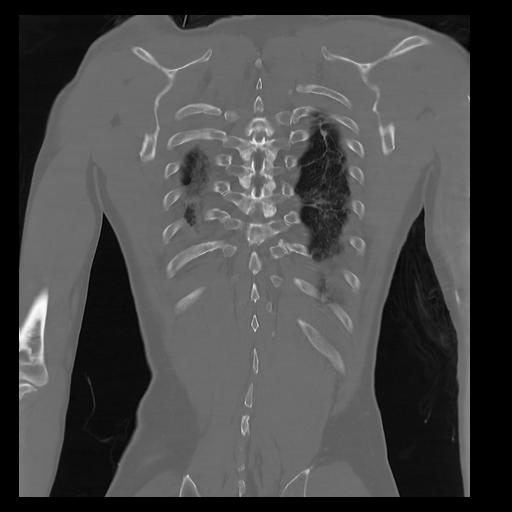

32 PULMON,CE,Coronal,3.000,PULMON,Coronal,